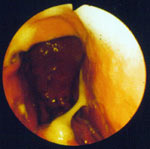

1. Hund mit länger andauerndem Erbrechen. Bei der endoskopischen Untersuchung des Magens wird die starke Entzündung der Magenwand sichtbar (linker und hintere Bildteil)